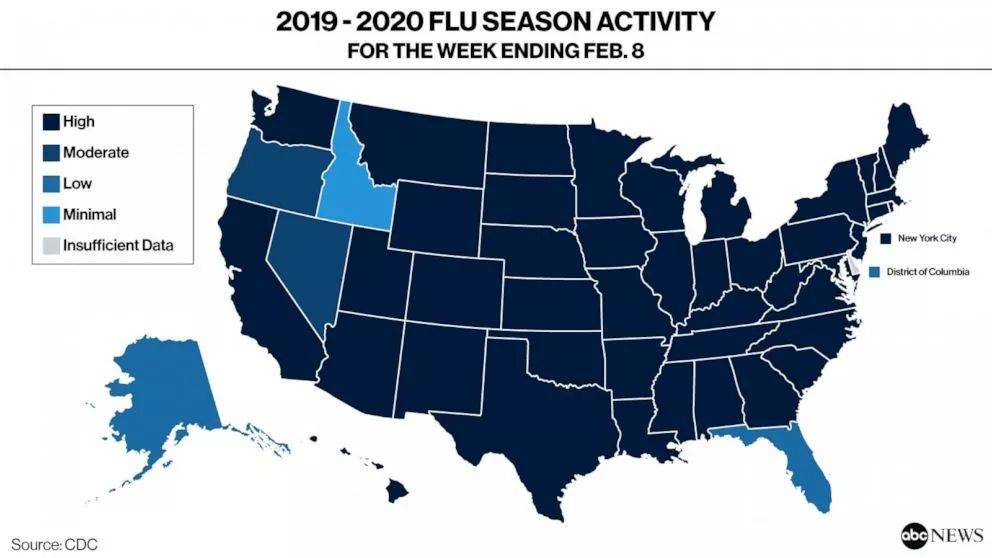

2020年是让人闻风丧胆的一年,这地狱般的开局里还有美国的流感。

据美国疾控中心CDC估计,自2019年流感季开始以来,到2020年2月8日。美国至少有

2600万人感染,其中有25万人需要住院治疗,14000人死亡(包括因并发症死亡的人数)。

除了美国本土各个地区都中招了,疫情甚至从美国扩散到了欧洲。